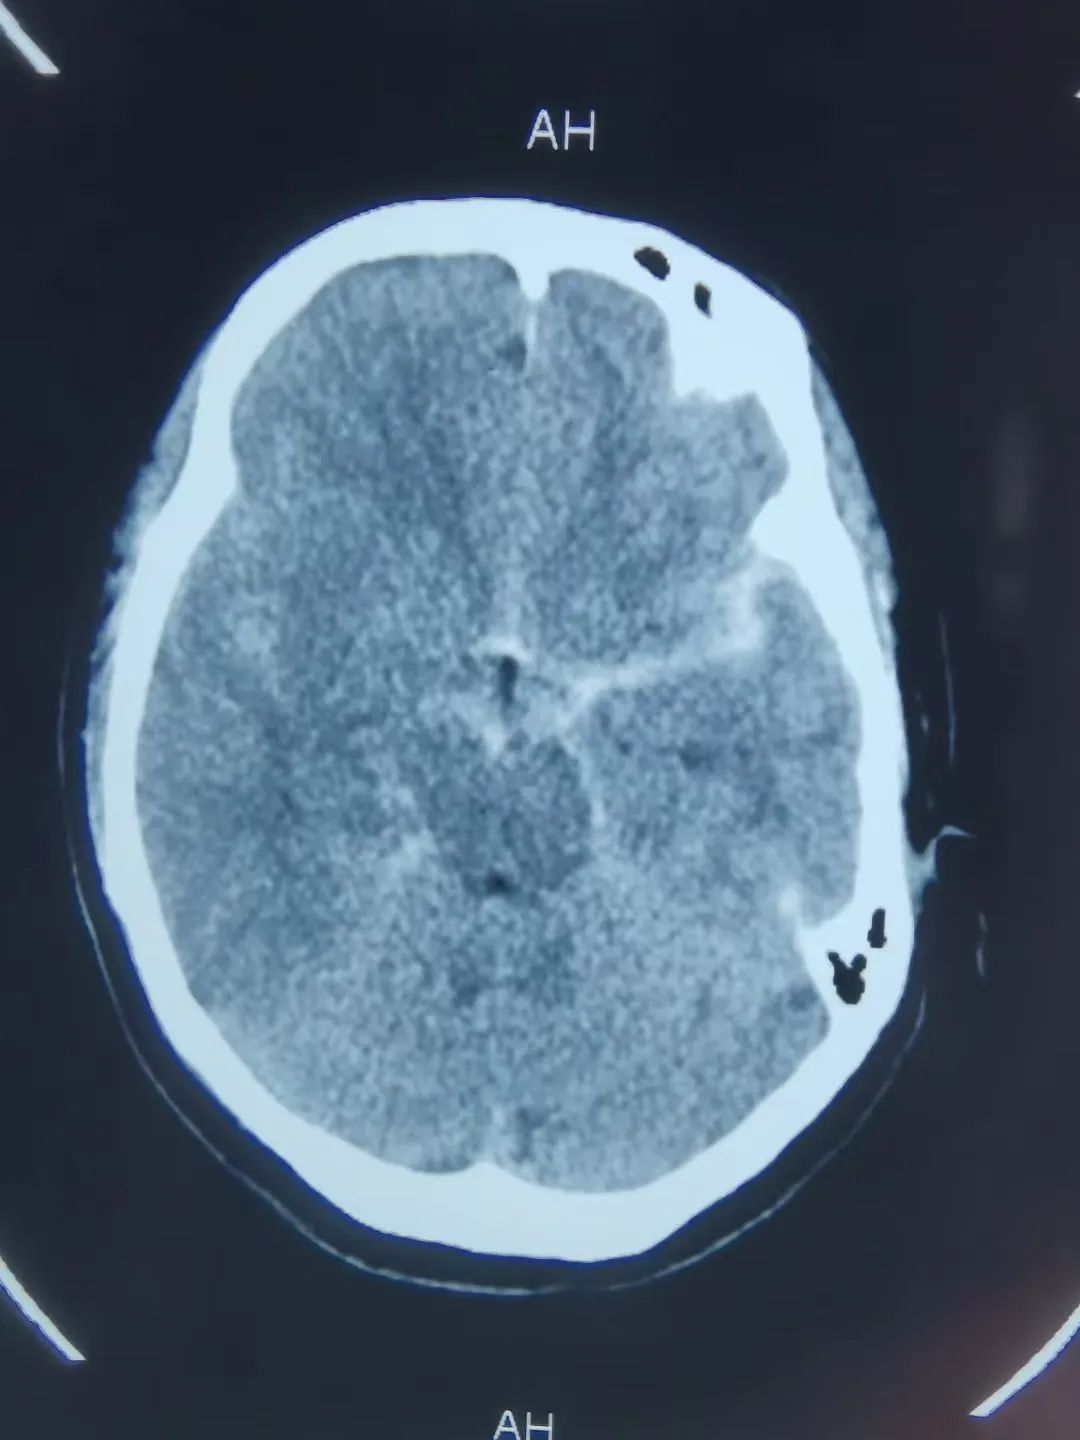

50歲的劉女士五天前深夜突發(fā)劇烈頭痛,不能忍受,伴惡心、嘔吐數(shù)次,家人急送醫(yī)院檢查。神經(jīng)外科主任施宏飛接診患者,結(jié)合患者病情、體格檢查及相關(guān)CT結(jié)果,診斷其蛛網(wǎng)膜下腔出血明確,為盡快明確患者病因,立即開(kāi)辟綠色通道行急診頭顱CTA,顯示左側(cè)后交通動(dòng)脈瘤。

施宏飛主任帶領(lǐng)神經(jīng)外科介入團(tuán)隊(duì)針對(duì)患者病情,緊急討論考慮蛛網(wǎng)膜下腔出血為動(dòng)脈瘤破裂所致出血。動(dòng)脈瘤是由于動(dòng)脈壁的病變或損傷,形成動(dòng)脈壁局限性或彌漫性擴(kuò)張或膨出的表現(xiàn)。顱內(nèi)動(dòng)脈瘤管壁比正常血管壁薄,易破裂出血,破裂后引發(fā)蛛網(wǎng)膜下腔出血,患者多表現(xiàn)為難以忍受的頭痛,是急危重癥疾病,死亡率極高。

蛛網(wǎng)膜下腔出血(SAH)指腦底部或腦表面的病變血管破裂,血液直接流入蛛網(wǎng)膜下腔引起的一種臨床綜合征,又稱為原發(fā)性蛛網(wǎng)膜下腔出血,約占急性腦卒中的10%,是一種非常嚴(yán)重的常見(jiàn)疾病。